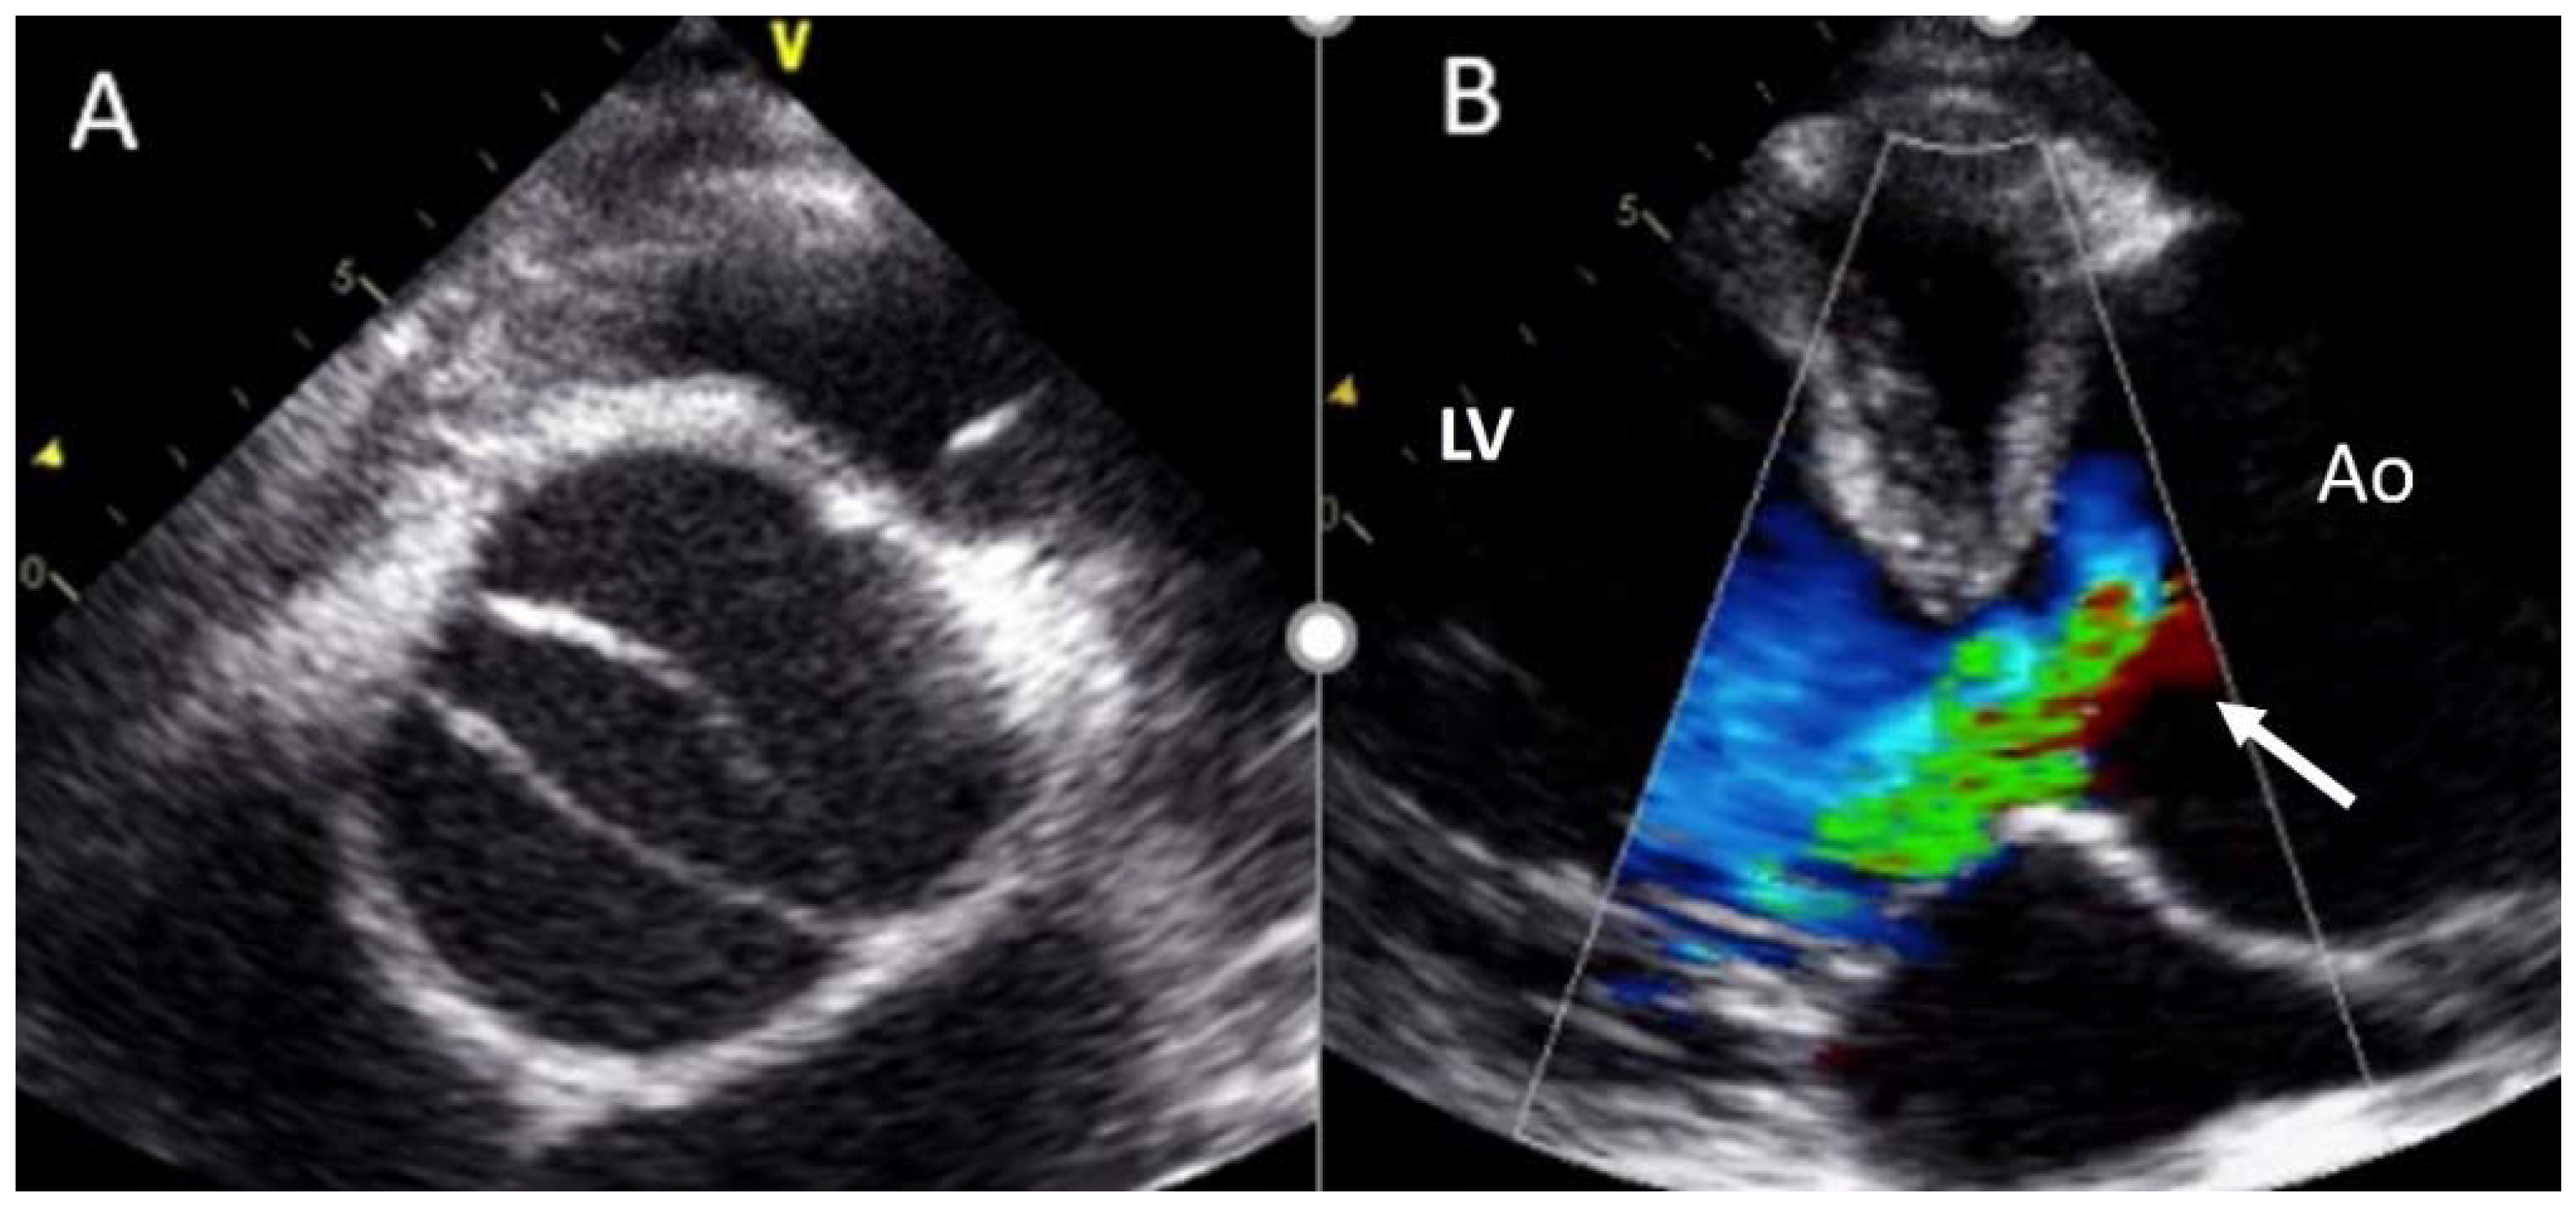

Multiple studies [53] have demonstrated that the segment that presents the maximum growth rate is the tubular ascending aorta (0.4 to 0.6 mm per year). This rate is influenced by age, baseline aorta diameter, associated valve dysfunction (regurgitation vs. stenosis), and location of the dilation (ascending versus root) [54,55]. Accumulated evidence shows that the root phenotype might represent a more severe form of aortopathy, possibly related to a genetic underlying condition that could contribute to the pathogenesis, especially if compared with the ascending phenotype. Furthermore, this root phenotype has been described to be associated with aortic events in the postoperative period of those who had undergone simple aortic valve replacement (Figure 7).

Figure 7.

(A) BAV RC−LC sigmoid fusion in a patient with Marfan syndrome. (B) Severe aortic root dilation and severe aortic regurgitation (arrow). Ao—aortic root; LV— left ventricle.